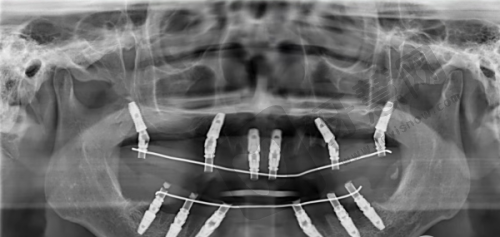

实例3:70岁陈大爷,半口无牙颌allon4种植,88000元重拾美食乐趣

陈大爷全口牙缺失多年,牙槽骨重度萎缩,传统种植需植骨3次。中大口腔王院长为其设计allon4即刻负重方案,上下颌各植入4颗植体,利用倾斜植体避开窦腔和神经管,当天戴上固定义齿。术后1周陈大爷就能吃软米饭,3个月后可啃苹果。他感叹:“以前喝稀饭都费劲,现在全家聚餐终于能夹菜了!”